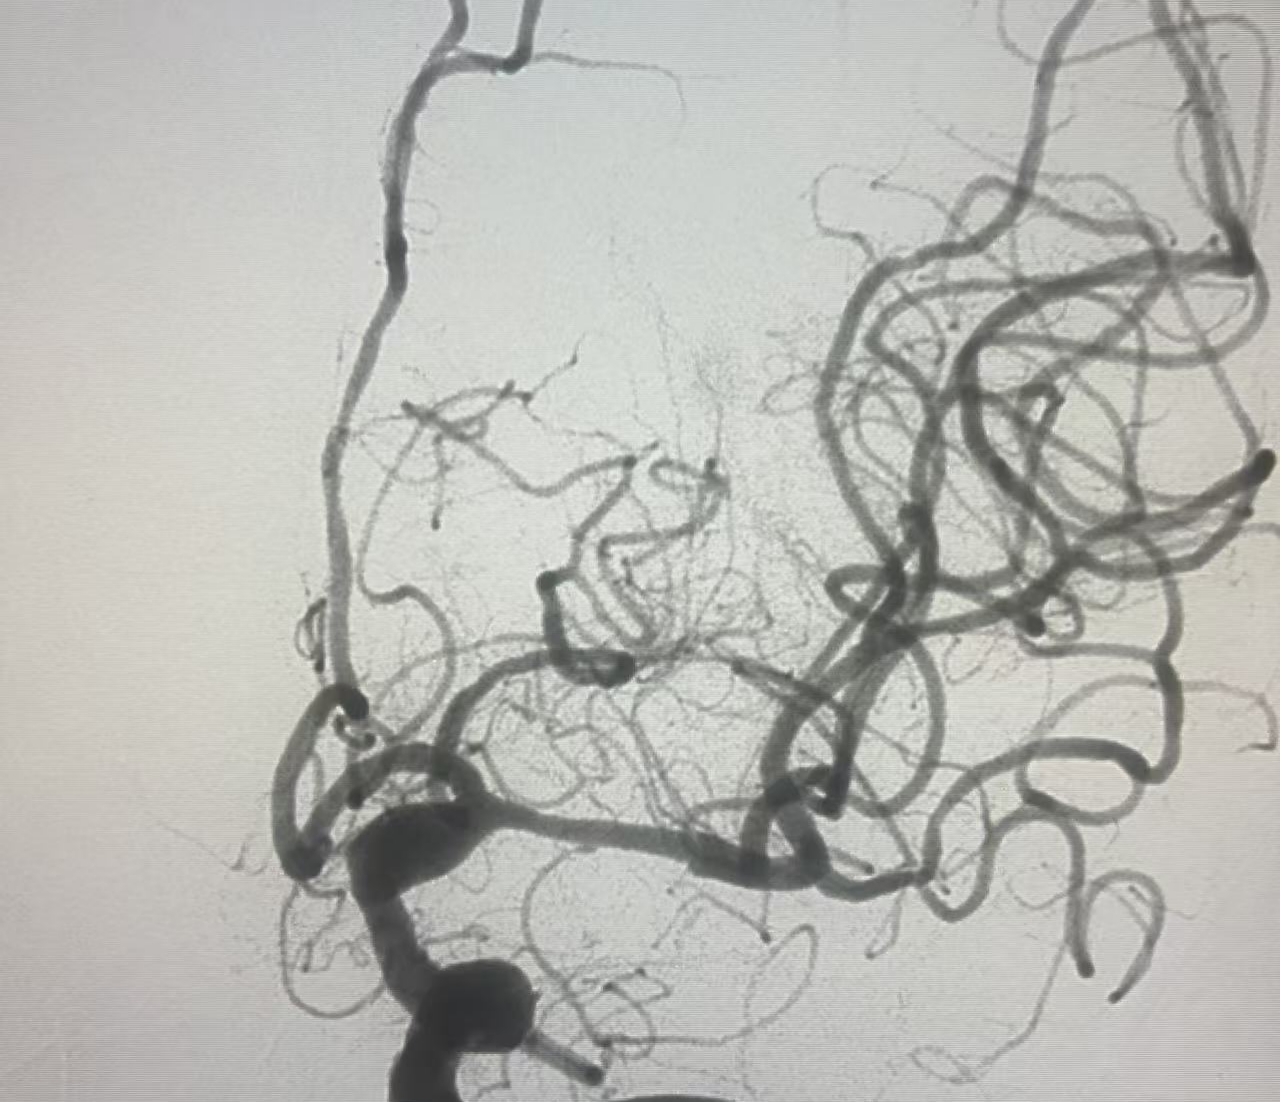

病例2:患者男,突发右侧肢体无力,伴言语不能活动5小时就诊,入院时浅昏迷,NIHSS评分:25分。接诊后,立即启动卒中绿色通道,积极完成术前评估,急诊行血管内治疗,术后患者恢复良好。

术中造影提示大脑中动脉完全闭塞

经中间导管抽吸,一把通畅,前向血流3级。